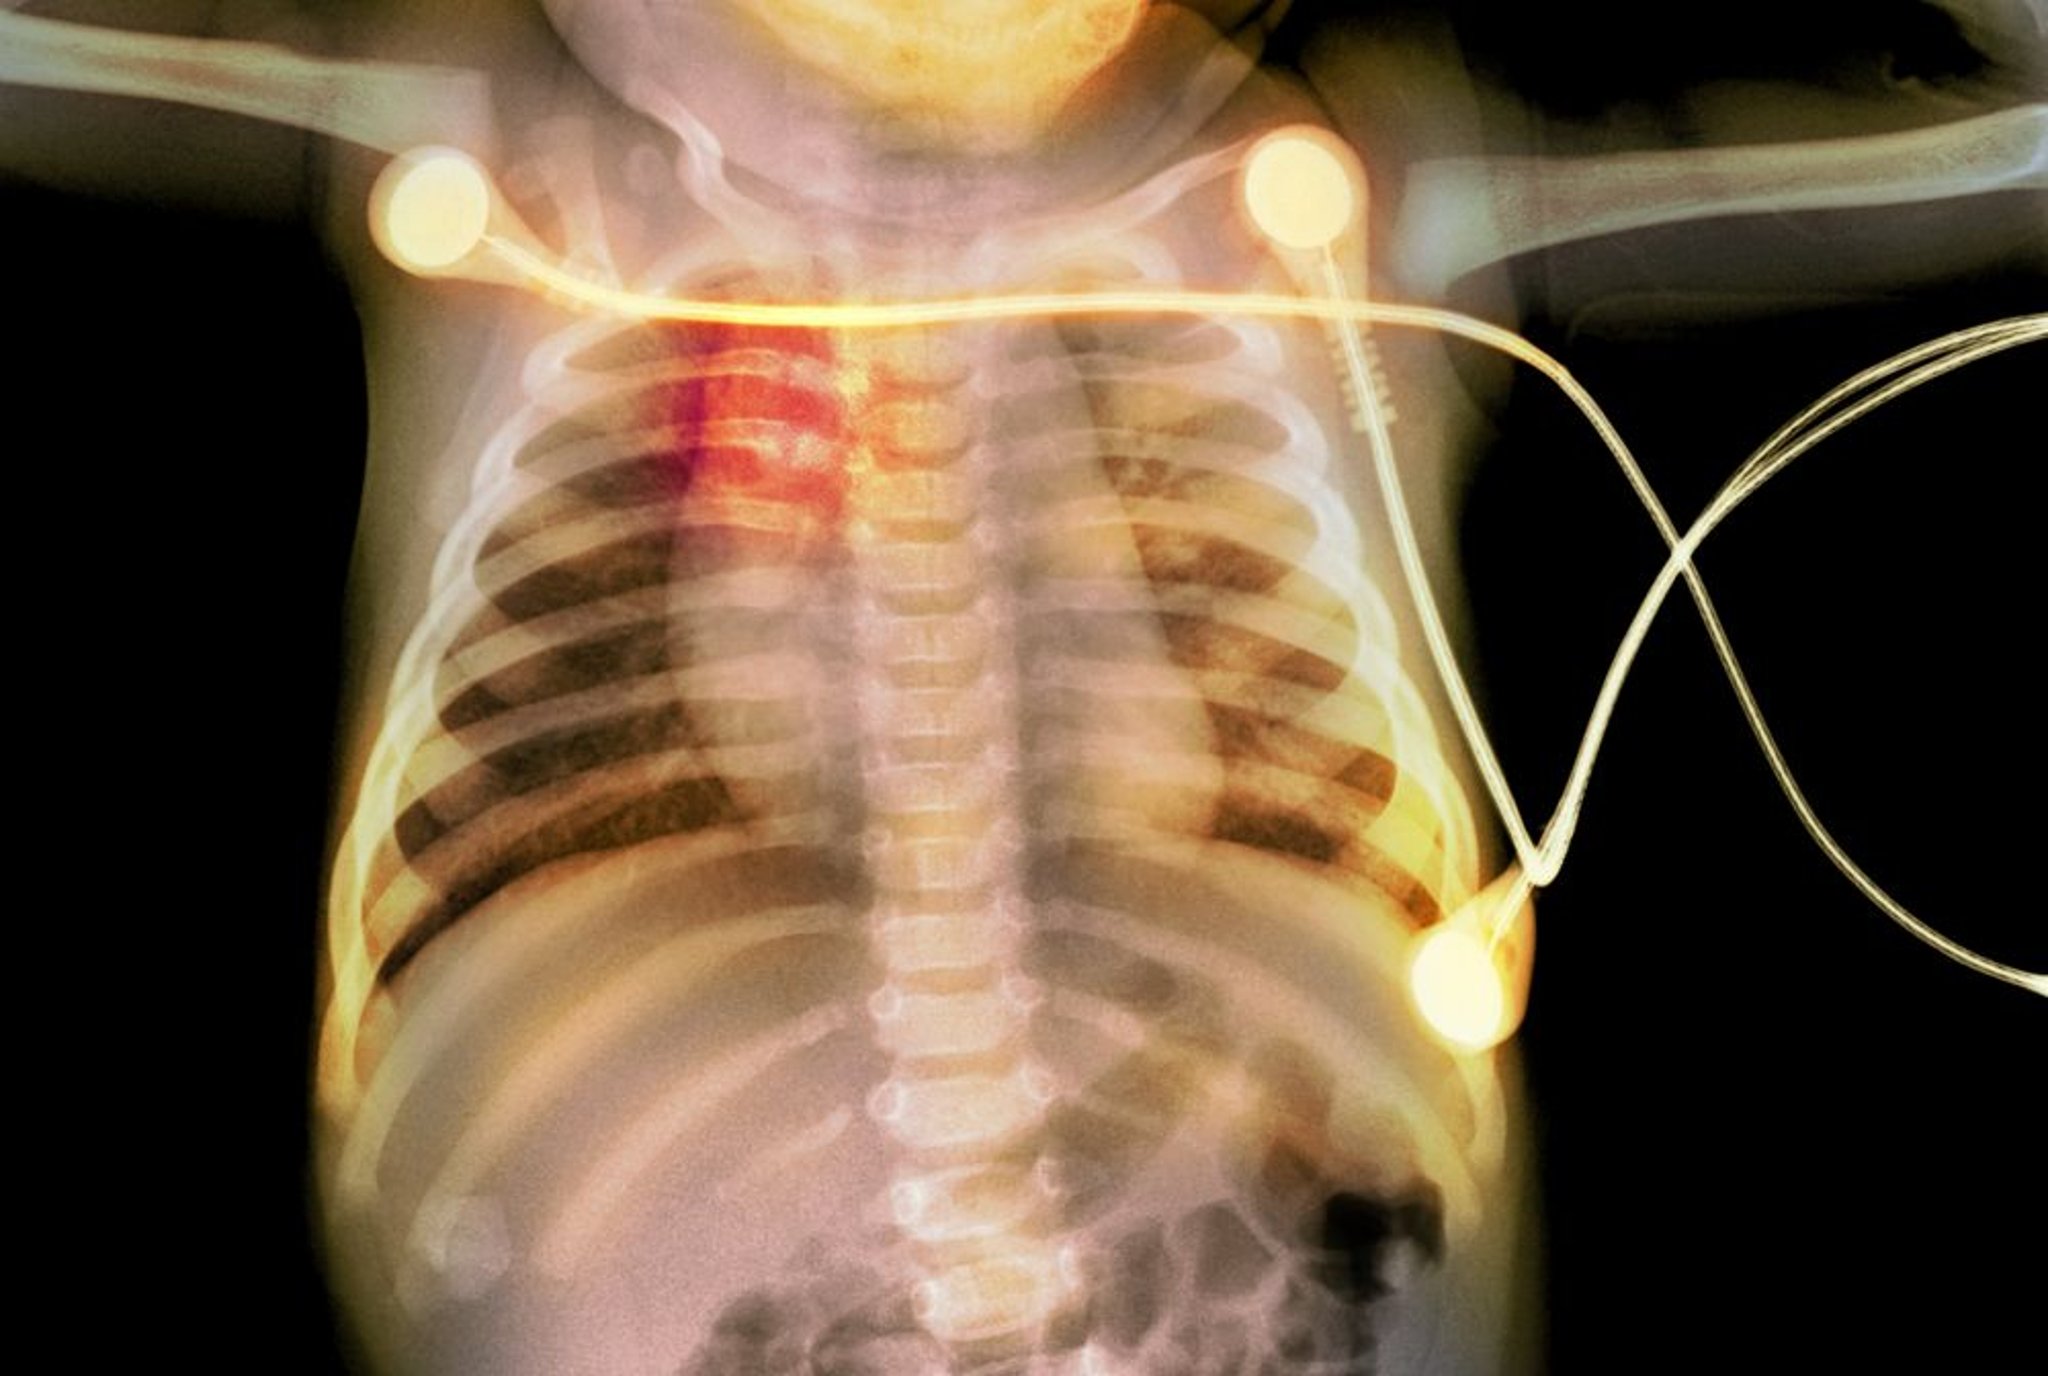

Fractures de côtes chez un nourrisson

Cette radiographie montre des fractures de côtes (surlignées en rouge) chez un nourrisson, évocatrices de maltraitance.

PHOTOSTOCK-ISRAEL/SCIENCE PHOTO LIBRARY